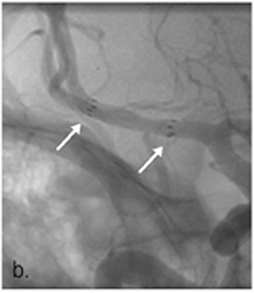

3. 경동맥 풍선 확장술 및 뇌혈관 스텐트 삽입술

<경동맥 풍선 확장술 및 뇌혈관 스텐트 삽입술>

- 신경중재(neurointervention)라는 용어는 다양한 신경계 질환을 두개골이나 척추골 절개 없이 영상 유도(image guidance)하에서 경피적으로 접근하여 치료하는 행위를 말하며, 뇌혈관에서도 동맥경화 등에 의한 협착증이 있을 경우 임상 양상을 고려하여 좁아진 혈관을 넓혀 주기 위해 풍선도관(balloon catheter)을 이용한 혈관성형술을 하거나 필요한 경우 스텐트 삽입술을 실시하고 있습니다.

<경동맥 풍선 확장술 및 뇌혈관 스텐트 삽입술>